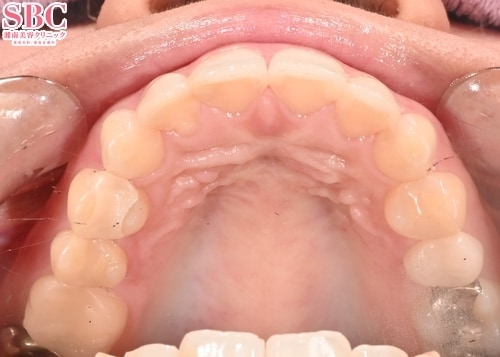

施術前

施術後7ヶ月後